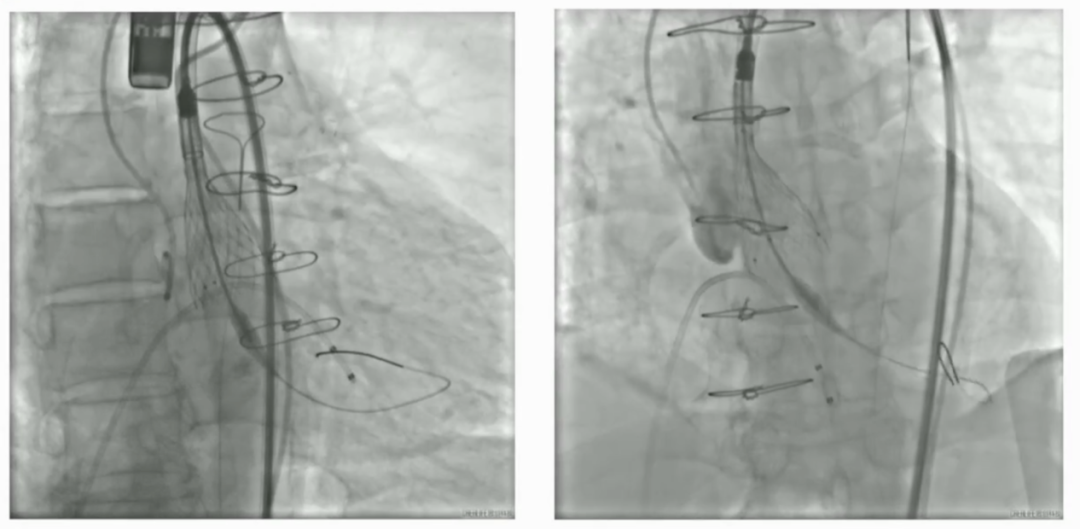

手术直播3:超大左房合并二尖瓣狭窄

本例患者存在严重心衰症状。心脏超声提示其左心房内径显著增大至176mm,属“超大左房”,并伴有重度二尖瓣狭窄,病情极为复杂危重。巨大的左房不仅显著增加了经房间隔穿刺及导管操作的技术难度与风险,也对术者建立稳定轨道、精准输送瓣膜的能力提出了极限挑战。

建立股静脉-房间隔-左房-左室-主动脉轨道

行二尖瓣球囊扩张

成功植入TAVR瓣膜